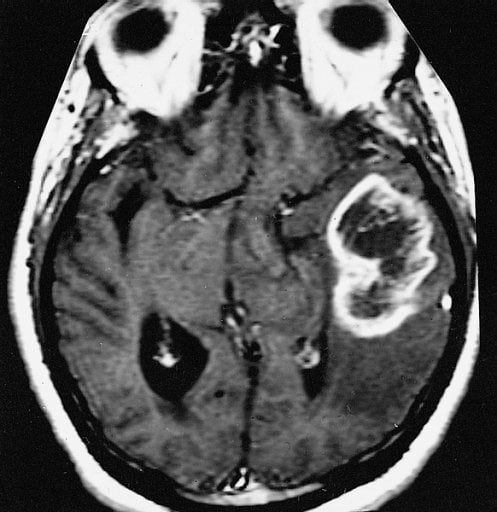

Researchers are discovering molecular pathways that might lead to new targeted therapies to potentially treat Glioblastoma, the most common and lethal form of brain cancer in adults. The image shows an MRI scan of a glioblastoma multiforme within an adult brain.